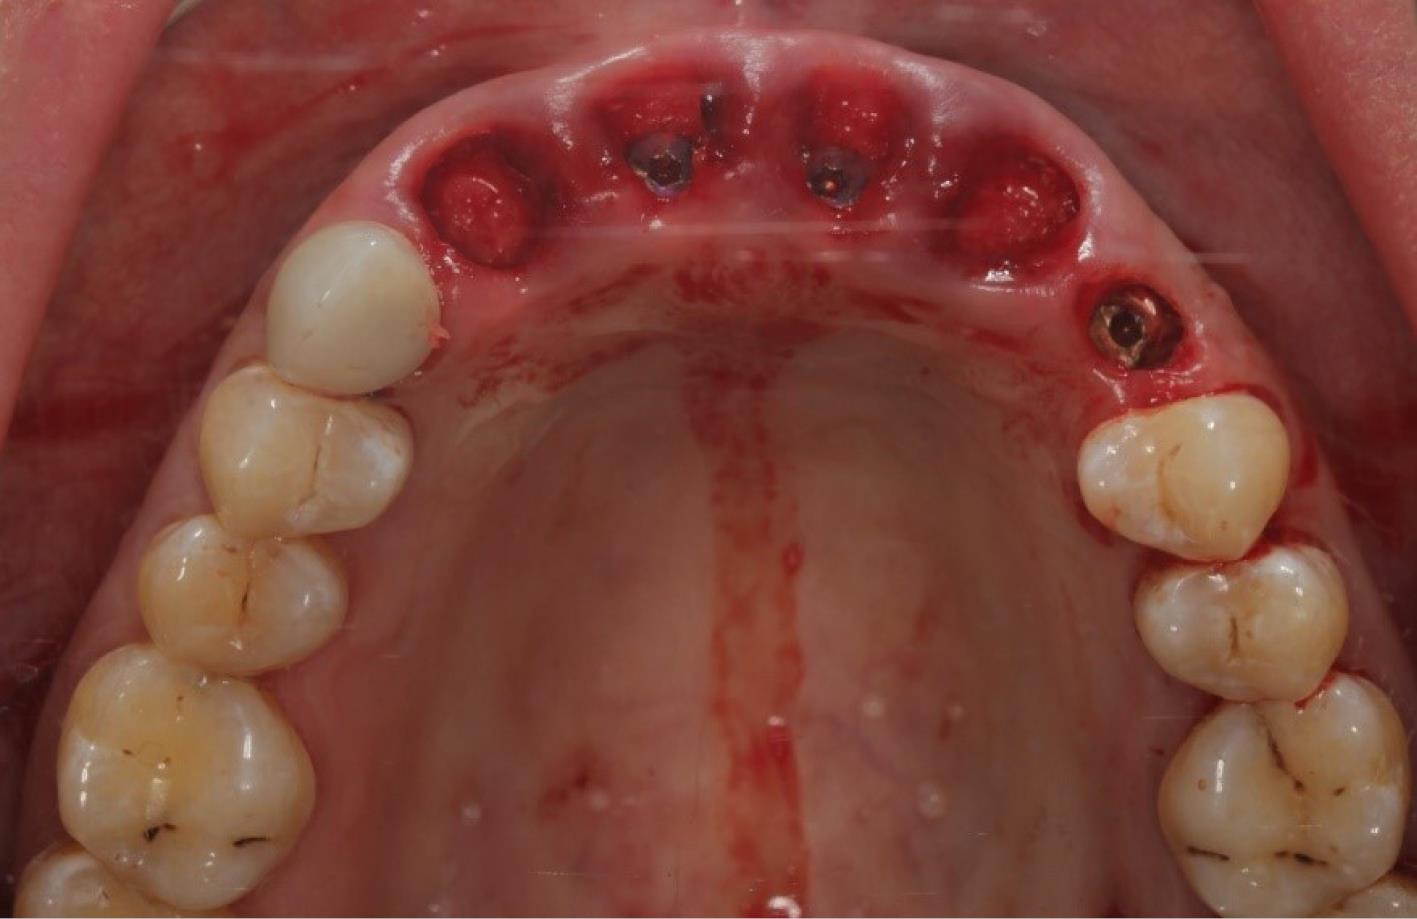

The procedure included three steps: tooth extraction, immediate implant placement, and peri-implant soft tissue surgery with a connective tissue graft from the maxillary tuberosity (Figures 1, 2, 3, and 4). A pocket was formed on the vestibular aspect of the implant to be placed, and its expansion was limited to preserve the integrity of the hard and soft tissues. Implants were placed according to standard surgical protocol with immediate insertion 3 mm apical to the mid-vestibular mucosal plane with a torque of 30, 45, and 55 Ncm. The bone quality of each patient was assessed during the procedure. Primary stability was achieved by virtue of the palatal wall. In the projection of the maxillary tuberosity, a full-thickness 2 × 2‒3-cm connective tissue graft was harvested and de-epithelialized. The soft tissue graft was fixed in the vestibule with interrupted sutures.

Figure 4.

Implant placement